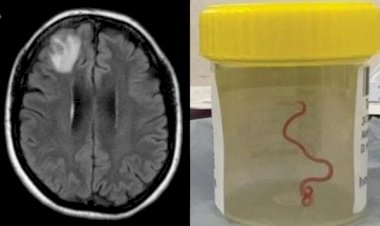

Verme de 8 cm é encontrado em cérebro humano pela primeira...

Uma mulher australiana foi acometida por um verme que usualmente só acomete as cobras...